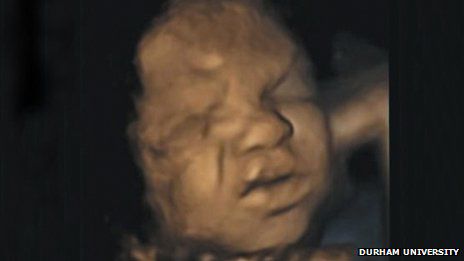

Już w brzuchu przyszłej mamy maleństwo uczy się komunikować za pomocą płaczu oraz grymasów twarzy - twierdzą badacze z Uniwersytetu Durham.

Ich szczegółowe badanie wykonane za pomocą USG pokazuje, że dzieci jeszcze przed przyjściem na świat wykonują mnóstwo ruchów twarzy - od uśmiechania się po obniżanie brwi czy marszczenie noska.